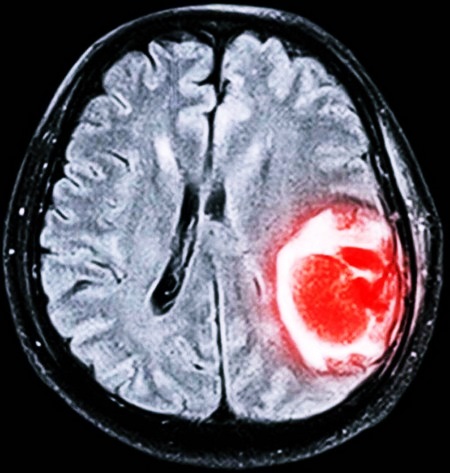

- Опухолевые процессы (рак), в частности глиобластома и киста, локализованные в различных отделах мозга, которые приводят к проблемам с оттоком ликвора или смещению структур мозга.

Для диагностики заболевания используются различные современные методы: МРТ, КТ, УЗИ и многие другие. Если форма патологии не молниеносная, то заподозрить наличие заболевания может невролог, который отметит прогресс ухудшения состояния больного, наращивание процессов нарушения сознания вместе с симптоматикой менингита.

Чтобы подтвердить диагноз, используются методы магнитно-резонансной и компьютерной томографии.